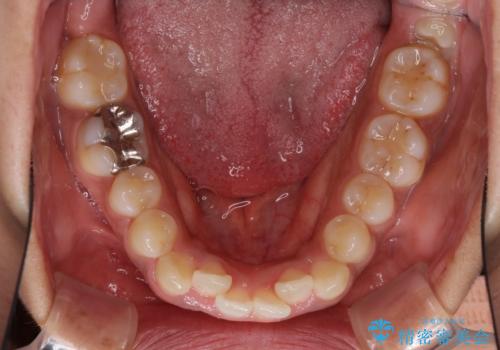

- 上下前歯の叢生を気にして来院された患者様です。

当初はインビザラインにて治療を開始しましたが、自己管理による治療が難しくなり、ワイヤー矯正へ転換して継続しました。

2年ほどインビザライン矯正を続けましたが、終了することができず、ワイヤーへ転換後は1年弱で終えることができました。